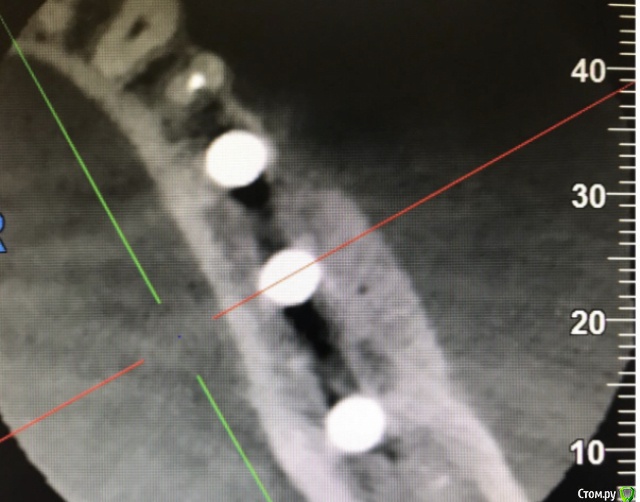

колесников Опубликовано 25 июня, 2020 Автор Поделиться Опубликовано 25 июня, 2020 Подтянуть первую ко второй или вторую к первой?). Аугментат созрел и интегрирован-в этом суть контрольного снимка,снимок «до» даёт понимание по объёму и форме дефекта. Вот так выглядит свежий графт (1),вот так созревший (2). И поперечные срезы. Все это уже давно запротезировано. Ссылка на комментарий